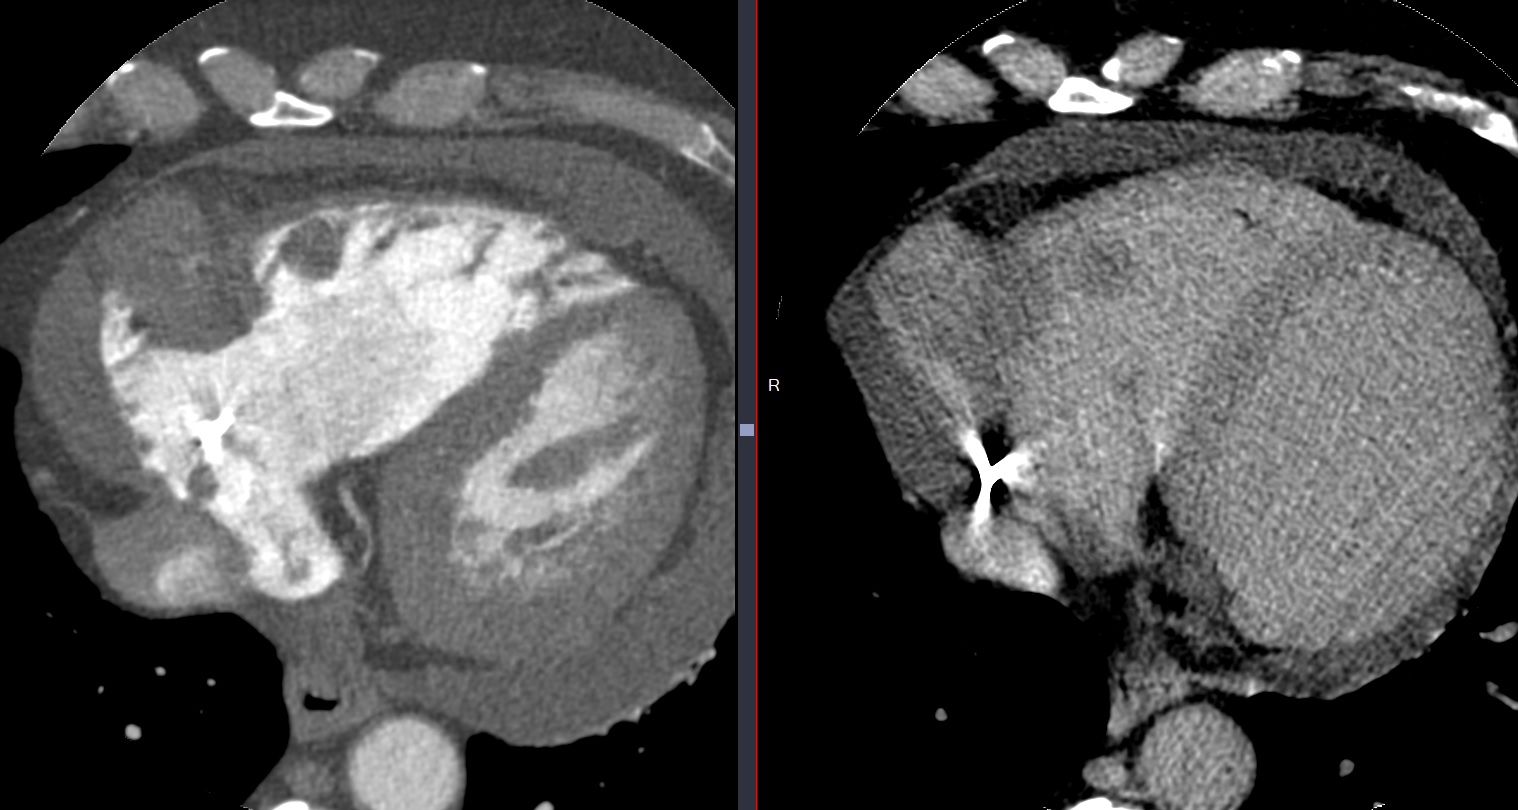

Metastase myocardique melanome progressif

Metastase myocardique melanome progressif